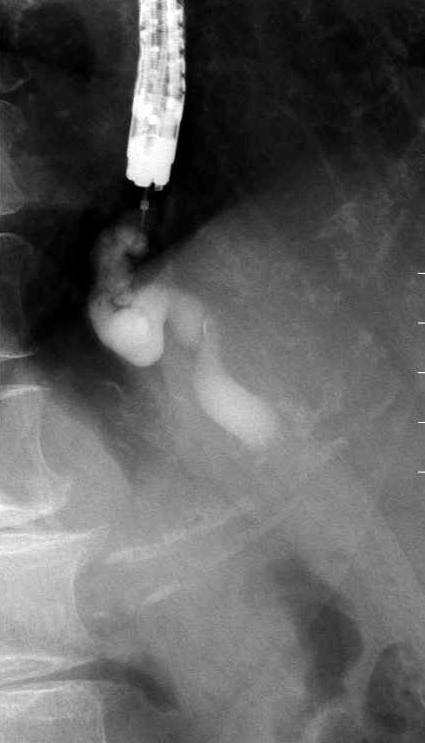

内視鏡的静脈瘤造影(endoscopic varicealography during injection sclerotherapy:EVIS)

内視鏡的硬化療法(EIS)(図[ID0608])のX線透視像。硬化剤が供血路に逆行性に注入されている。